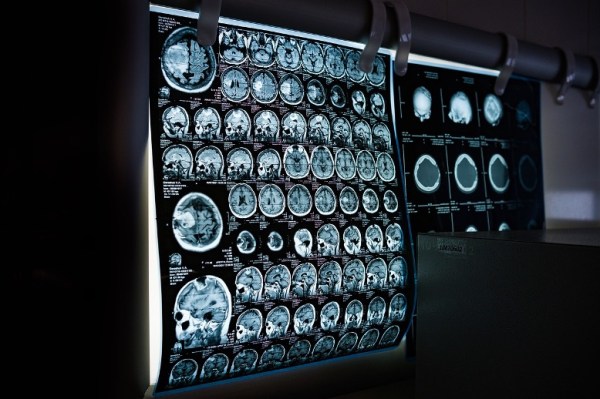

How the ability to visualize the human brain has revolutionized neuroscience, and what comes next

Researchers have only been able to easily visualize the human brain in the last couple decades. Learn how that has changed the course of neuroscience research and what we might be able to do next.